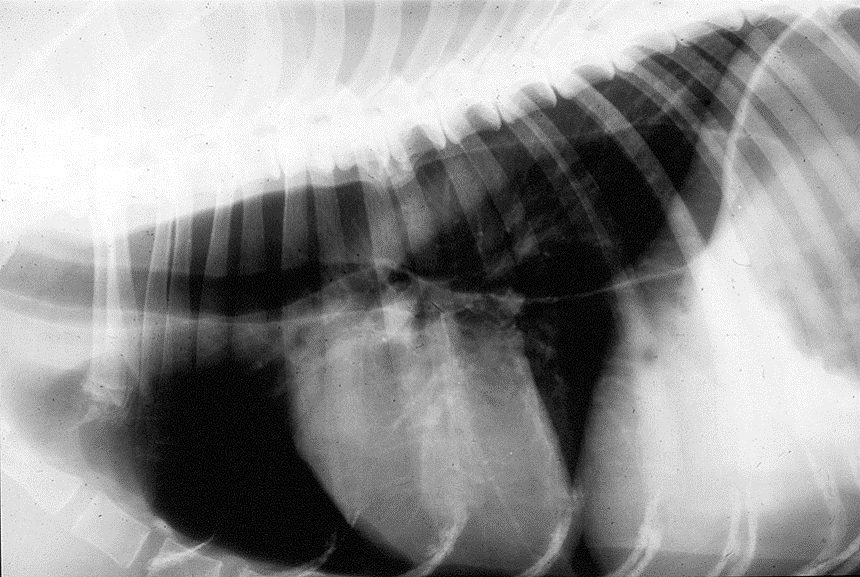

Plain lateral thoracic radiograph

What is the issue here?

Large oesophagus